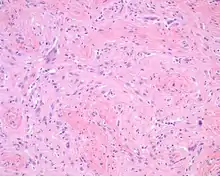

The overlying skin or squamous mucosa is intact and uninvolved by the process. There is normal glial tissue set within a fibrous connective tissue stroma. There is such blending, that the underlying process may be difficult to detect without special studies. In a few cases, large gemistocytes, neurons, choroid plexus, ependyma, and retinal pigmented cells may be seen.[2][3]

Histochemistry

A trichrome stain will highlight the dual components well, with the glial tissue staining red, while the background fibrosis stains a bright blue.[2]

Immunohistochemistry

The glial tissue is highlighted with S100 protein and with glial fibrillary acidic protein, although the latter is much more sensitive for glial tissue.[2]